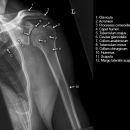

Scapula lateral (tangential, Leer-Larché)

Indikation

Impingementsyndrom und Rotatorenmanschettenläsion

Indikationen und Beurteilungskriterien

- Rotatorenmanschettenruptur (2,3): acromiohumerale Abstand <10 mm = Humeruskopf-Hochstand (< 10 mm verdächtig, < 6 mm beweisend). Knöcherne Vorsprünge am Schulterdach oder Oberarmkopf?, Methode der 1. Wahl = Sonographie

- Impingementsyndrom (2): Neigungswinkel des Acromions? Je gebogener bzw. hakenförmiger desto wahrscheinlicher ist ein Impingment, Zystenbildung im Bereich des Tuberculum majus, Subchondrale Sklerosierung des Tuberculum majus und subakromiale Osteophytenbildung (v.a. bei Beziehung zum Ursprung des Lig. acromioclaviculare), Sehnenverkalkungen (Supraspinatussehne)?

- bei Luxationen: Anteriore Luxation, Posteriore Luxation

- CAVE: Begleitverletzungen? (-> heute umfassend mit CT/MRT zu beurteilen)

- Hill- Sachs Läsion = Dorsokraniale Humeruskopf- Impressionsfraktur (50%) (Aufnahme der 1. Wahl: Stryker oder CT)

- umgekehrte Hill-Sachs Läsion = anteromediale Impression nach hinterer Luxation

- Bankart-Läsion: Abriss des vorderen Labrum-Kapsel-Komplexes bzw. Abrissfraktur des vorderen unteren Glenoidrandes (-> CT-Athrographie, Arthro-MRT)

- Tuberculum majus (15%), Pfannenrand